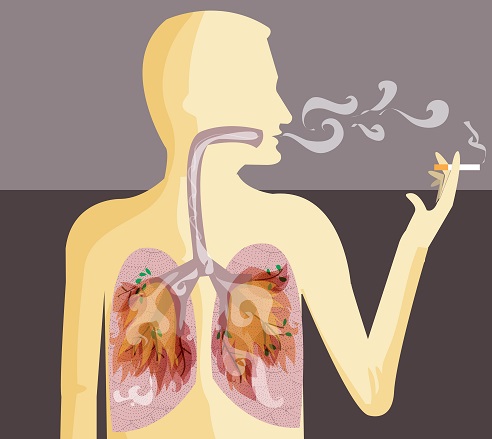

폐암은 국내 암 사망률 1위로, 과거에는 흡연이 폐암의 주요 원인이었지만 최근에는 비흡연자의 폐암 발병이 크게 증가하고 있습니다. 폐암은 오랜 기간 암 사망률 1위를 차지하고 있지만, 의학의 발전으로 생존율이 높아지고 있습니다. 그러나 초기 단계에서 올바르게 관리하는 것이 중요합니다. 폐암의 초기 징후가 무엇인지, 폐암에 좋은 음식은 무엇인지 알아두는 것이 좋습니다.

흡연자와 비흡연자를 비교하면 흡연자는 폐암에 걸릴 확률이 낮게는 15배, 높게는 80배까지 높아질 수 있고, 폐암의 마지막 원인 중 하나이기 때문에 흡연자라면 금연을 하는 것이 정말 좋습니다.

또한 흡연의 경우 간접흡연으로 인해 주변 비흡연자에게도 영향을 미칠 수 있으므로 주의해야 합니다. 담배를 피우지 않는다면 야채와 과일을 충분히 섭취하는 것이 좋습니다. 신선할수록 좋으며, 이는 영양소를 섭취하고 시간이 지남에 따라 면역 체계를 구축할 수 있는 좋은 방법입니다.